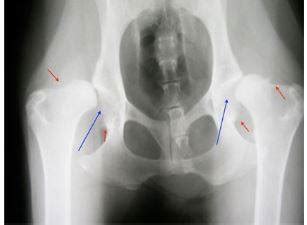

Počas vývoja plemena došlo, žiaľ, v niektorých fázach k príbuzenskej plemenitbe. Takto sa vyvinuli rôzne dedičné ochorenia. U československého vlčiaka sa častejšie vyskytuje dysplázia bedrového kĺbu. U renomovaných chovateľov sa však všetkým šteniatkam robia vyšetrenia na vylúčenie náchylnosti na toto ochorenie.